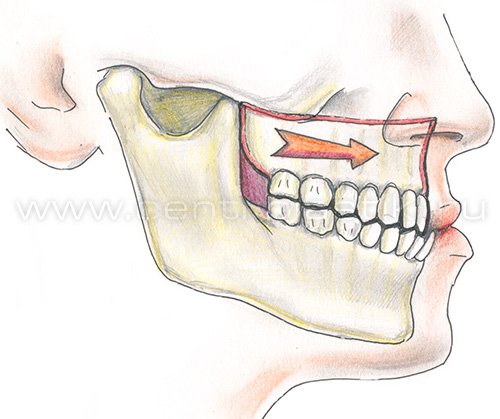

Остеотомия верхней челюстиПоказания Коррекция аномалий развития верхней челюсти (микрогнатия, ретрогнатия верхней челюсти). Остеотомию на верхней челюсти проводят как этап ортодонтического лечения. Операция Остеотомия верхней челюсти выполняется внутриротовым доступом под эндотрахеальным наркозом, выполняется разрез слизистой оболочки полости рта и надкостницы, разрез производят несколько выше переходной складки верхней челюсти от 7 до 7 зубов. Края раны раздвигаются, тем самым осуществляется доступ к передней стенке верхней челюсти.  На передних и боковых стенках верхней челюсти слева и справа производятся разметки линий распилов.  Специальными пилками проводится остеотомия по разметкам.  Затем отделяется распиленный фрагмент и перемещается в заранее выбранное положение.   Фиксация перемещенного фрагмента в новом положении осуществляется титановыми мини-пластинками.  Длительность Операция занимает от 1,5 до 3 часов и проводится под наркозом. В течение 1 месяца после лечения сохраняется отечность мягких тканей лица, может отмечаться нарушение чувствительности верхней губы и щек, чувствительность восстанавливается самопроизвольно через некоторое время. В ряде случаев после операции для обеспечения хорошего срастания костей проводят межчелюстное шинирование , верхняя и нижняя челюсти фиксируются друг к другу специальными приспособлениями, так что полное открытие рта невозможно. В этот период (2-3 недели) возможно питание только протертой и жидкой пищей. После операции остеотомии верхней челюстиВ послеоперационном периоде возможно ношение ортодонтической брекет системы для правильного смыкания зубных рядов верхней и нижней челюстей. Реабилитационный период В течение 1-3 суток после операции рекомендовано нахождение в стационаре под наблюдением медицинского персонала (длительность нахождения в стационаре может быть продлена до 10 суток в зависимости от течения послеоперационного периода). Длительность реабилитационного периода зависит от восстановительных способностей организма. Эффективность Окончательный результат операции можно наблюдать через 3-6 месяцев. В послеоперационном периоде могут сохраняться отеки в течение 2-4 недель, в зависимости от индивидуальных особенностей восстановление протекает с разной скоростью. |